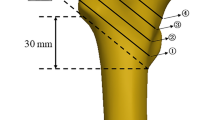

A total of 89 human ribs from 13 donors were prepared for experimental testing, while solely ribs from levels 4 to 8 were included since highest fracture rates were detected at these levels in a recent retrospective study19. Donor age ranged from 55 to 99 years with a mean of 75 years, including seven male and six female donors and a total of 45 left and 44 right ribs (Table 1). The use of the specimens was approved by the ethics committee board of the University of Ulm (vote no. 92/20). The specimens were acquired from body donation programs which require legally valid informed consents from a parent or legal guardian (Science Care Inc., Phoenix, USA; Anatomy Gifts Registry program, Hanover, USA). All methods were performed in accordance with relevant guidelines and regulations and following the Declaration of Helsinki. Rib cage specimens were gathered fresh frozen and stored at − 20 °C. Prior to preparation, bone quality was assessed by CT scans (Somatom Definition AS, Siemens Healthcare, Erlangen, Germany) with a resolution of 512 × 512x804 pixels and a voxel size of 0.87 × 0.87x0.6 mm in terms of bone mineral density of the respective spines. The bone mineral density values were evaluated from the trabecular bones of the lumbar vertebral bodies L2, L3, and L4 using standard clinical density-reference phantoms (Osteo Phantom, Siemens Healthineers, Erlangen, Germany), which were included in the patient table of the CT device and averaged for every specimen, while the calibration curves were automatically fitted using a standardized software protocol for clinical evaluation, comparable to the procedure of a previous investigation26. After thawing the specimens at 5 °C for about 12 h, the ribs were separated from the spines by cutting the connecting ligaments. All muscular and ligamentous tissues were carefully removed and the costal cartilage was severed close to the cartilage-bone junction. Ribs showing any signs of bony defects, previous fractures, or degeneration were excluded from the study. Rib heads and shafts were coaxially embedded in a polymethylmethacrylate cylinder (Technovit 3040, Heraeus Kulzer, Wehrheim, Germany) for a length of about 40 mm, while care was taken that the rib was uniformly surrounded by PMMA to ensure rigid fixation in the testing device. After preparation, the ribs were frozen again and stored at − 20 °C in sealed polyethylene bags in order to keep the exposure to room temperature to the same time period for all ribs. Prior to testing, every rib was thawed for about 12 h in 0.9% saline solution. Immediately before testing, remaining tendon tissue and the periosteum were carefully removed using fine sandpaper while taking care not to damage bone substance. In the next step, the ribs were primed with a thin layer of white water-based paint and sprayed with a black speckle pattern for surface strain measurement with digital image correlation (Fig. 4). This speckle technique was verified in a preliminary study not to affect the biomechanical properties of biological tissue27.

After each trial, fracture type and location were visually assessed and documented. Cross-sectional rib morphology was acquired using micro-CT scans (Skyscan 1172 Micro-CT, Skyscan, Kontich, Belgium) of about 10 mm long samples, which were cut posteriorly from the fracture position and as closely as possible to the fracture site, respectively. The scans were performed using a tube voltage of 100 kV, a tube current of 100 µA, an Al-Cu filter for beam hardening reduction, and a scan period of 38 min, obtaining an isotropic voxel size of 5 µm. The following parameters were examined using a standard threshold technique for greyscale values within the software CTAn 1.17.7.2 (Skyscan, Kontich, Belgium) in combination with a calibration phantom (Bruker MicroCT, Kontich, Belgium): Bone volume/tissue volume ratio, average thickness, number, and separation of the trabeculae, average cortical thickness, and area moments of inertia Ixx and Iyy around the longitudinal (xx) and transverse (yy) cross-sectional axes (Fig. 6). All values were automatically calculated by the software for every cross-section and finally averaged for a determined region of interest over 50 adjacent sample slices. Thickness values were defined as the minimum thickness at different locations of the respective area. Ixx and Iyy were defined as the integral of the quadratic distance of all bony elements to the axes xx and yy over the cross-sectional bony area, reflecting potential resistance against bending deformation around these axes. Global morphology of the ribs was identified regarding rib length and width prior to embedding using a tape measure. Rib length was measured as both the external edge length, characterizing the length of the external rib side from rib head to anterior tip of the rib shaft, and the antero-posterior length, describing the direct distance between rib head and anterior tip of the rib shaft (Fig. 4). Rib width was defined as the maximum distance between the rib shaft and the connecting line between rib head and anterior tip of the rib shaft.